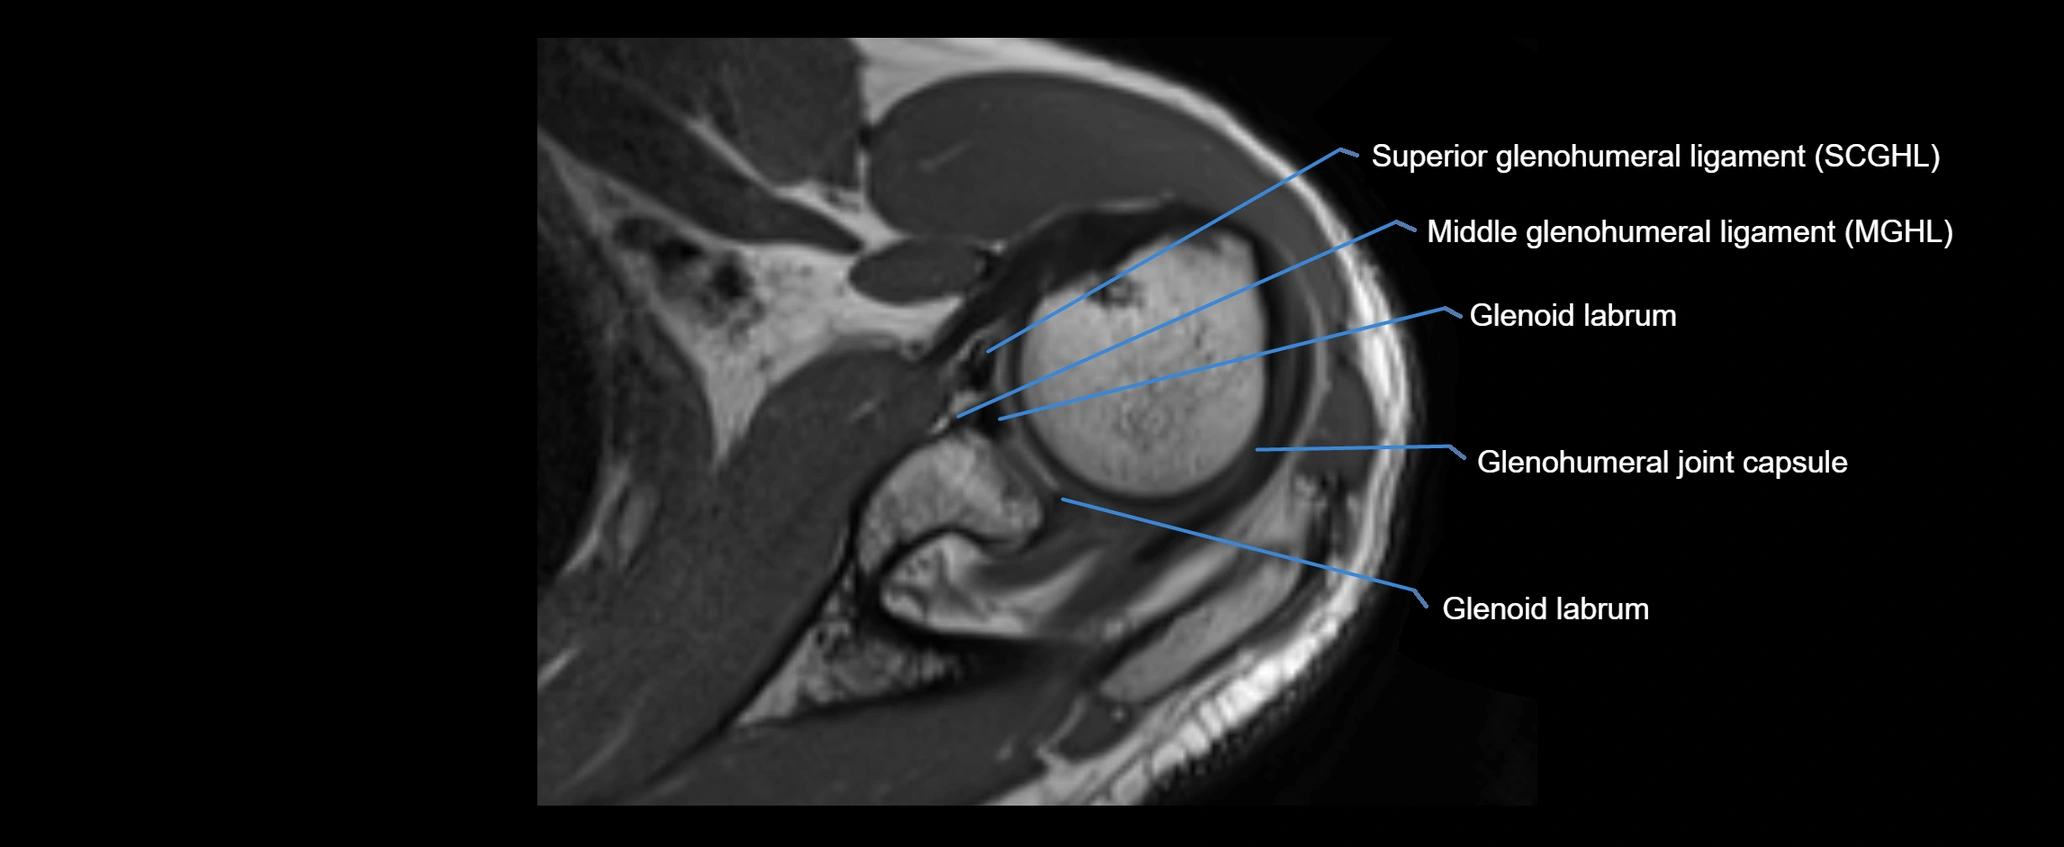

MRI images

image